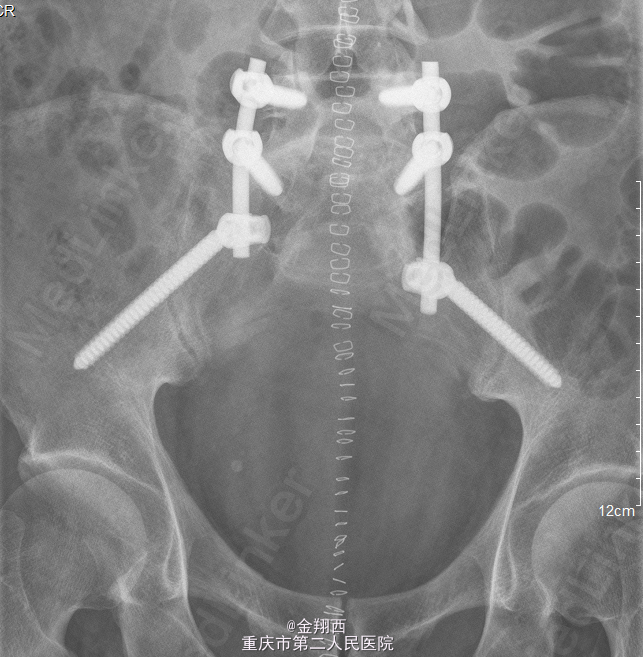

患者,男,51岁,因“腰骶部疼痛14月,伴麻木11月”入院。 患者14月前无明显诱因下出现腰骶部疼痛,程度不剧能忍,未予重视。11月前,腰骶部疼痛较前加剧,伴腰骶部及双侧大腿内侧麻木.

骶部轻压痛,双下肢感觉正常,肌力、肌张力正常,双侧病理反射未引出。MRI示::骶椎周围占位伴骶骨受侵,神经源性肿瘤可能大。

初步诊断:骶骨肿瘤。麻醉下行腹主动脉球囊阻断下骶骨肿瘤切除、内固定术。